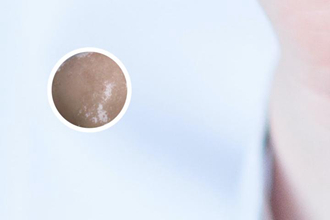

白點癲風(fēng),是一種以皮膚局部或全身出現(xiàn)大小不等的白色點狀或片狀脫色斑為特征的皮膚病。患者常常關(guān)心這種疾病是否會遺傳給下一代,因此我們來討論一下白點癲風(fēng)是否具有遺傳性。